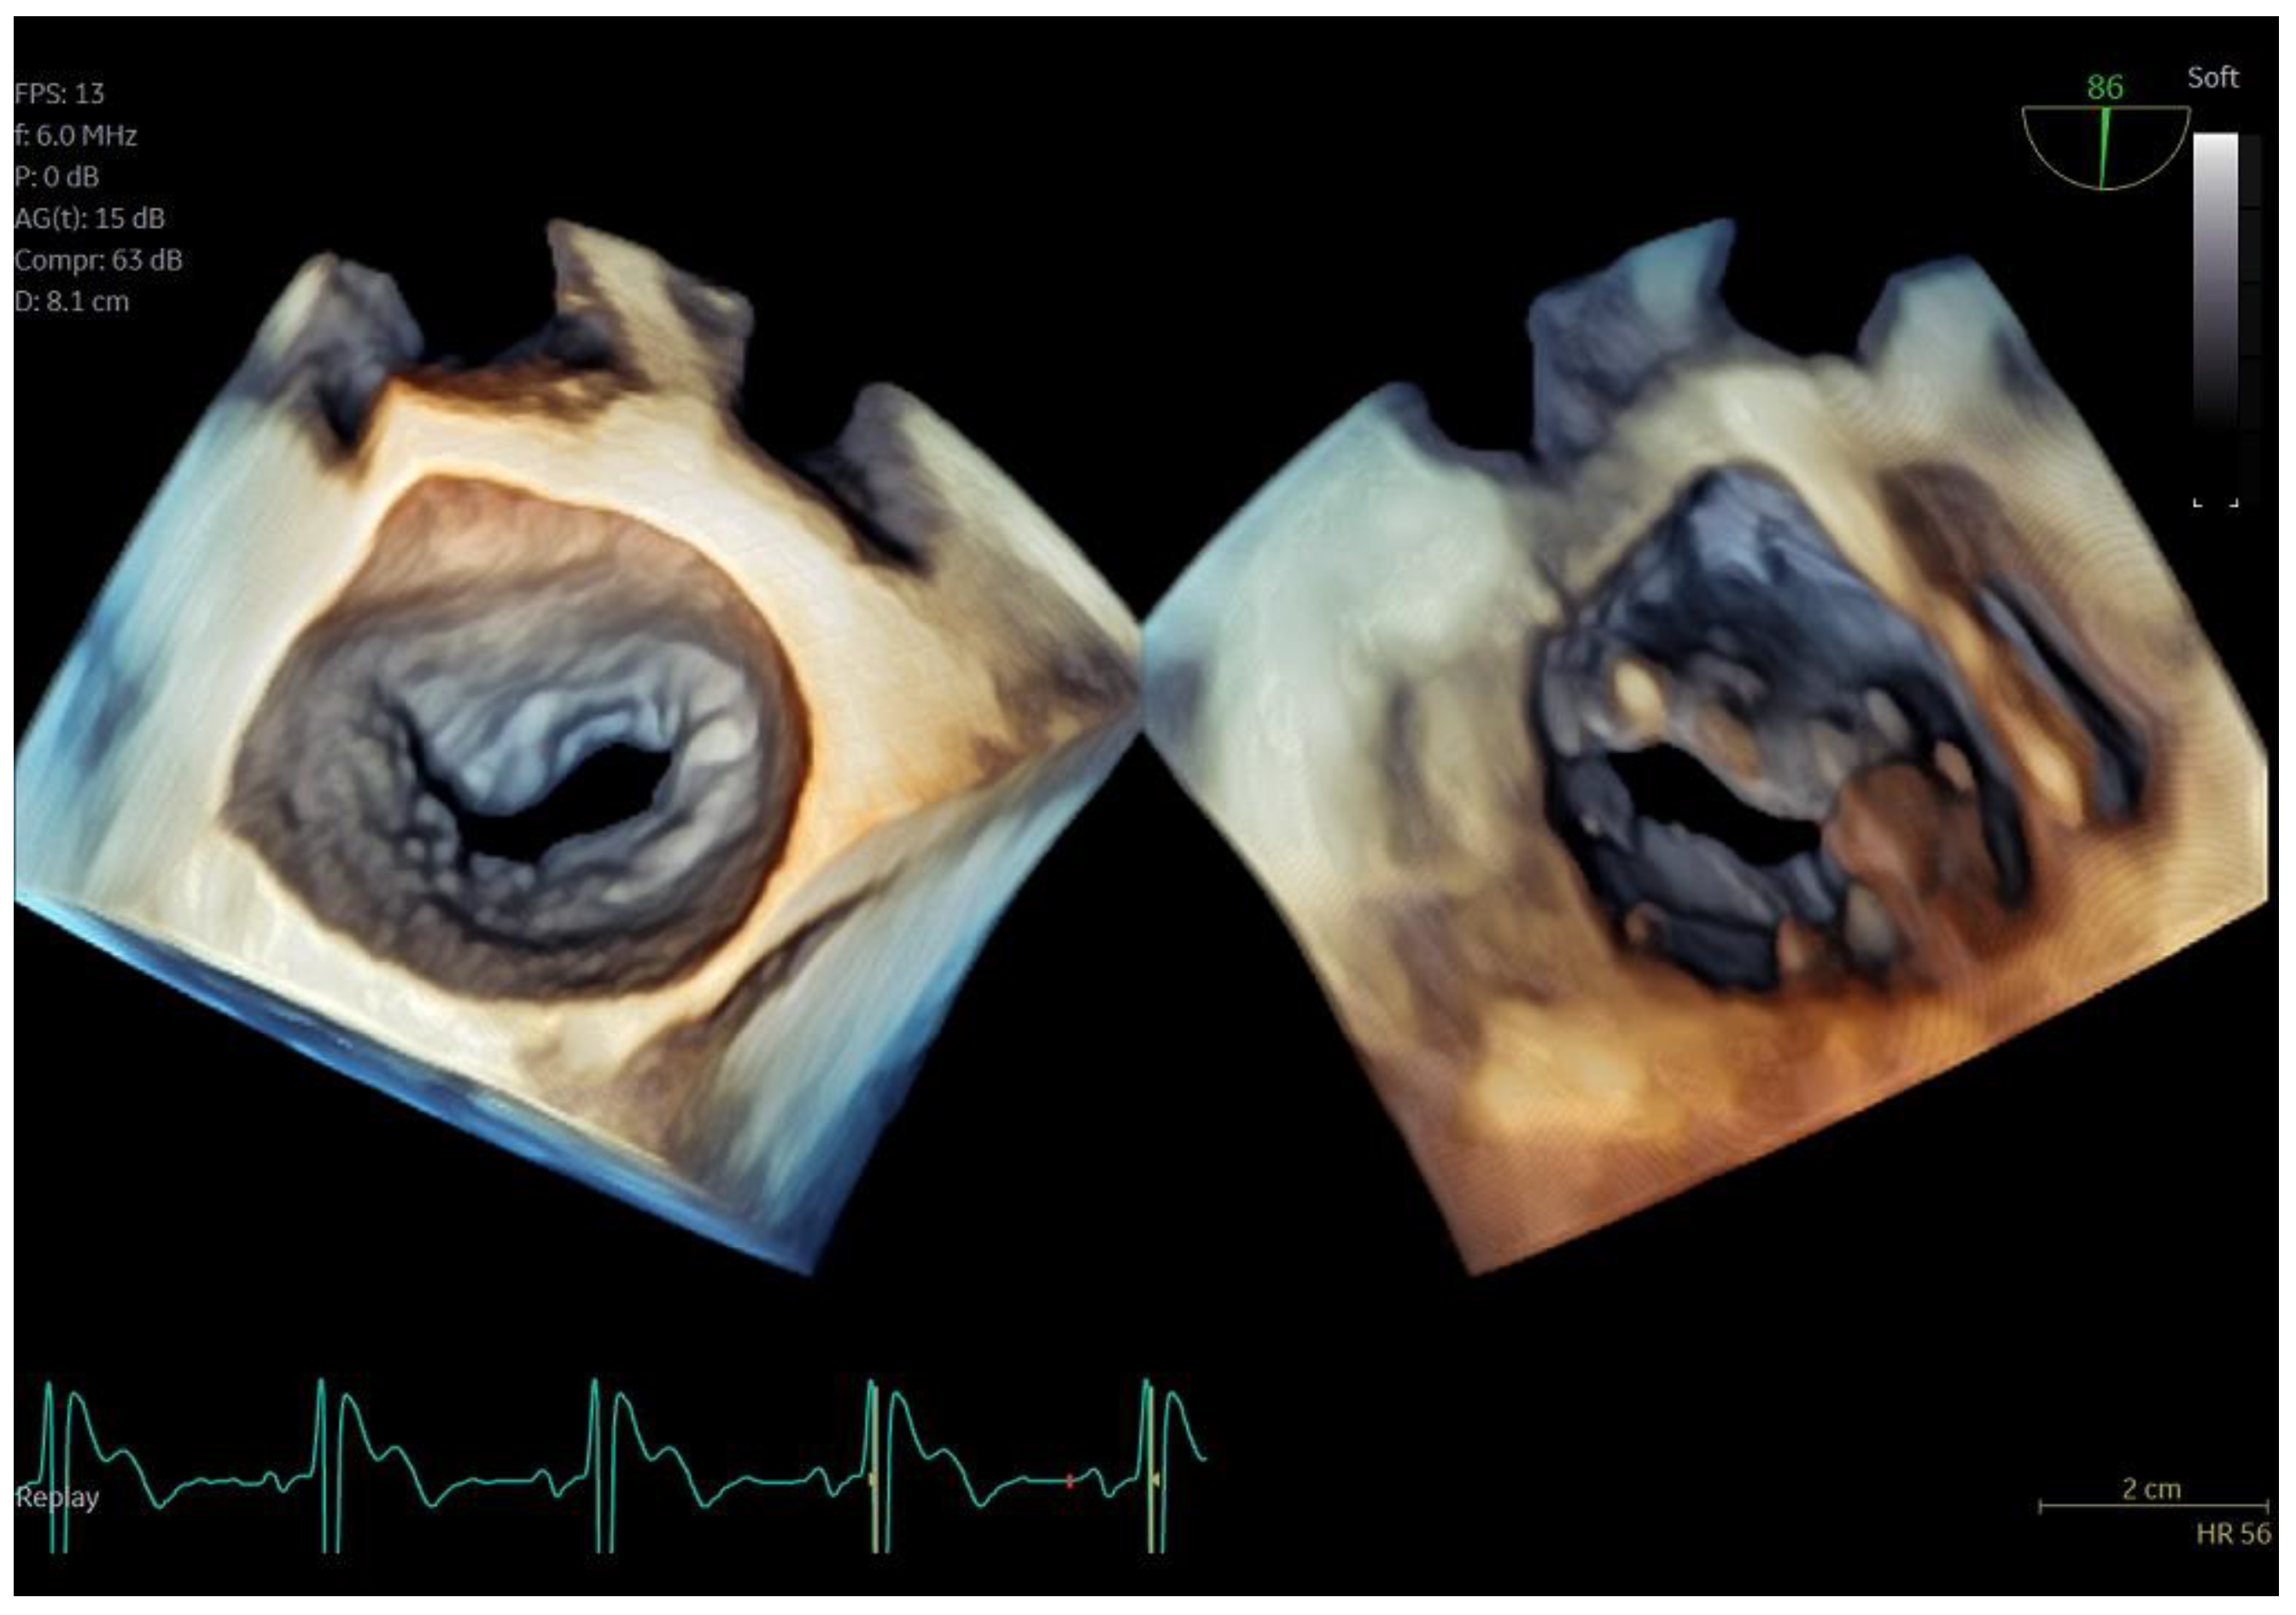

Figure 3.

Dual crop 3D volume-rendered atrial (left) and ventricular (right) views of normal mitral valve.